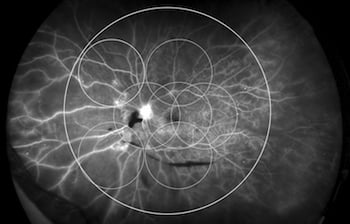

The core question posed by the study was whether the location of diabetic lesions in the retina could be of clinical significance. The study’s authors defined “anterior” diabetic retinopathy as being DR found entirely outside of a circle superimposed over the seven standard ETDRS fields. (See Figure 1.) Patients with DR entirely inside the 7SF circle were classified with “posterior” DR, and those with DR in and out of the circle were classified with “diffuse” DR.